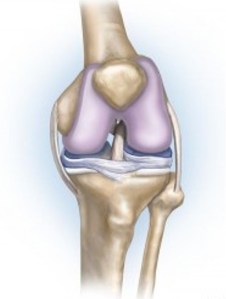

Let’s break this word down: osteo– refers to your bones, –arthr- refers to your joint, and –itis refers to inflammation and breakdown. So when we put this all together, osteoarthritis describes an inflammation and breakdown to the joint where two bones contact each other. While this could occur at any joint, it is most common (by far) in the knee joint.

Whether you are walking, running, climbing stairs, or getting out of a chair, your knee joint has to be able to support your entire body weight and move freely. It is able to do this because the bones which support your body weight are coated in an incredibly smooth, shock absorbing tissue called cartilage (if you want to learn more about this and other structures of the knee joint, click here). However, once you begin to develop osteoarthritis, this incredible cartilage begins to break down, become rough, and wear away. Over time, this breakdown will progress to a point where instead of supporting your body weight on a smooth cushion (your cartilage), you will be supporting your body weight on the rough ends of your bones. This is what your doctor means when they say “bone-on-bone”